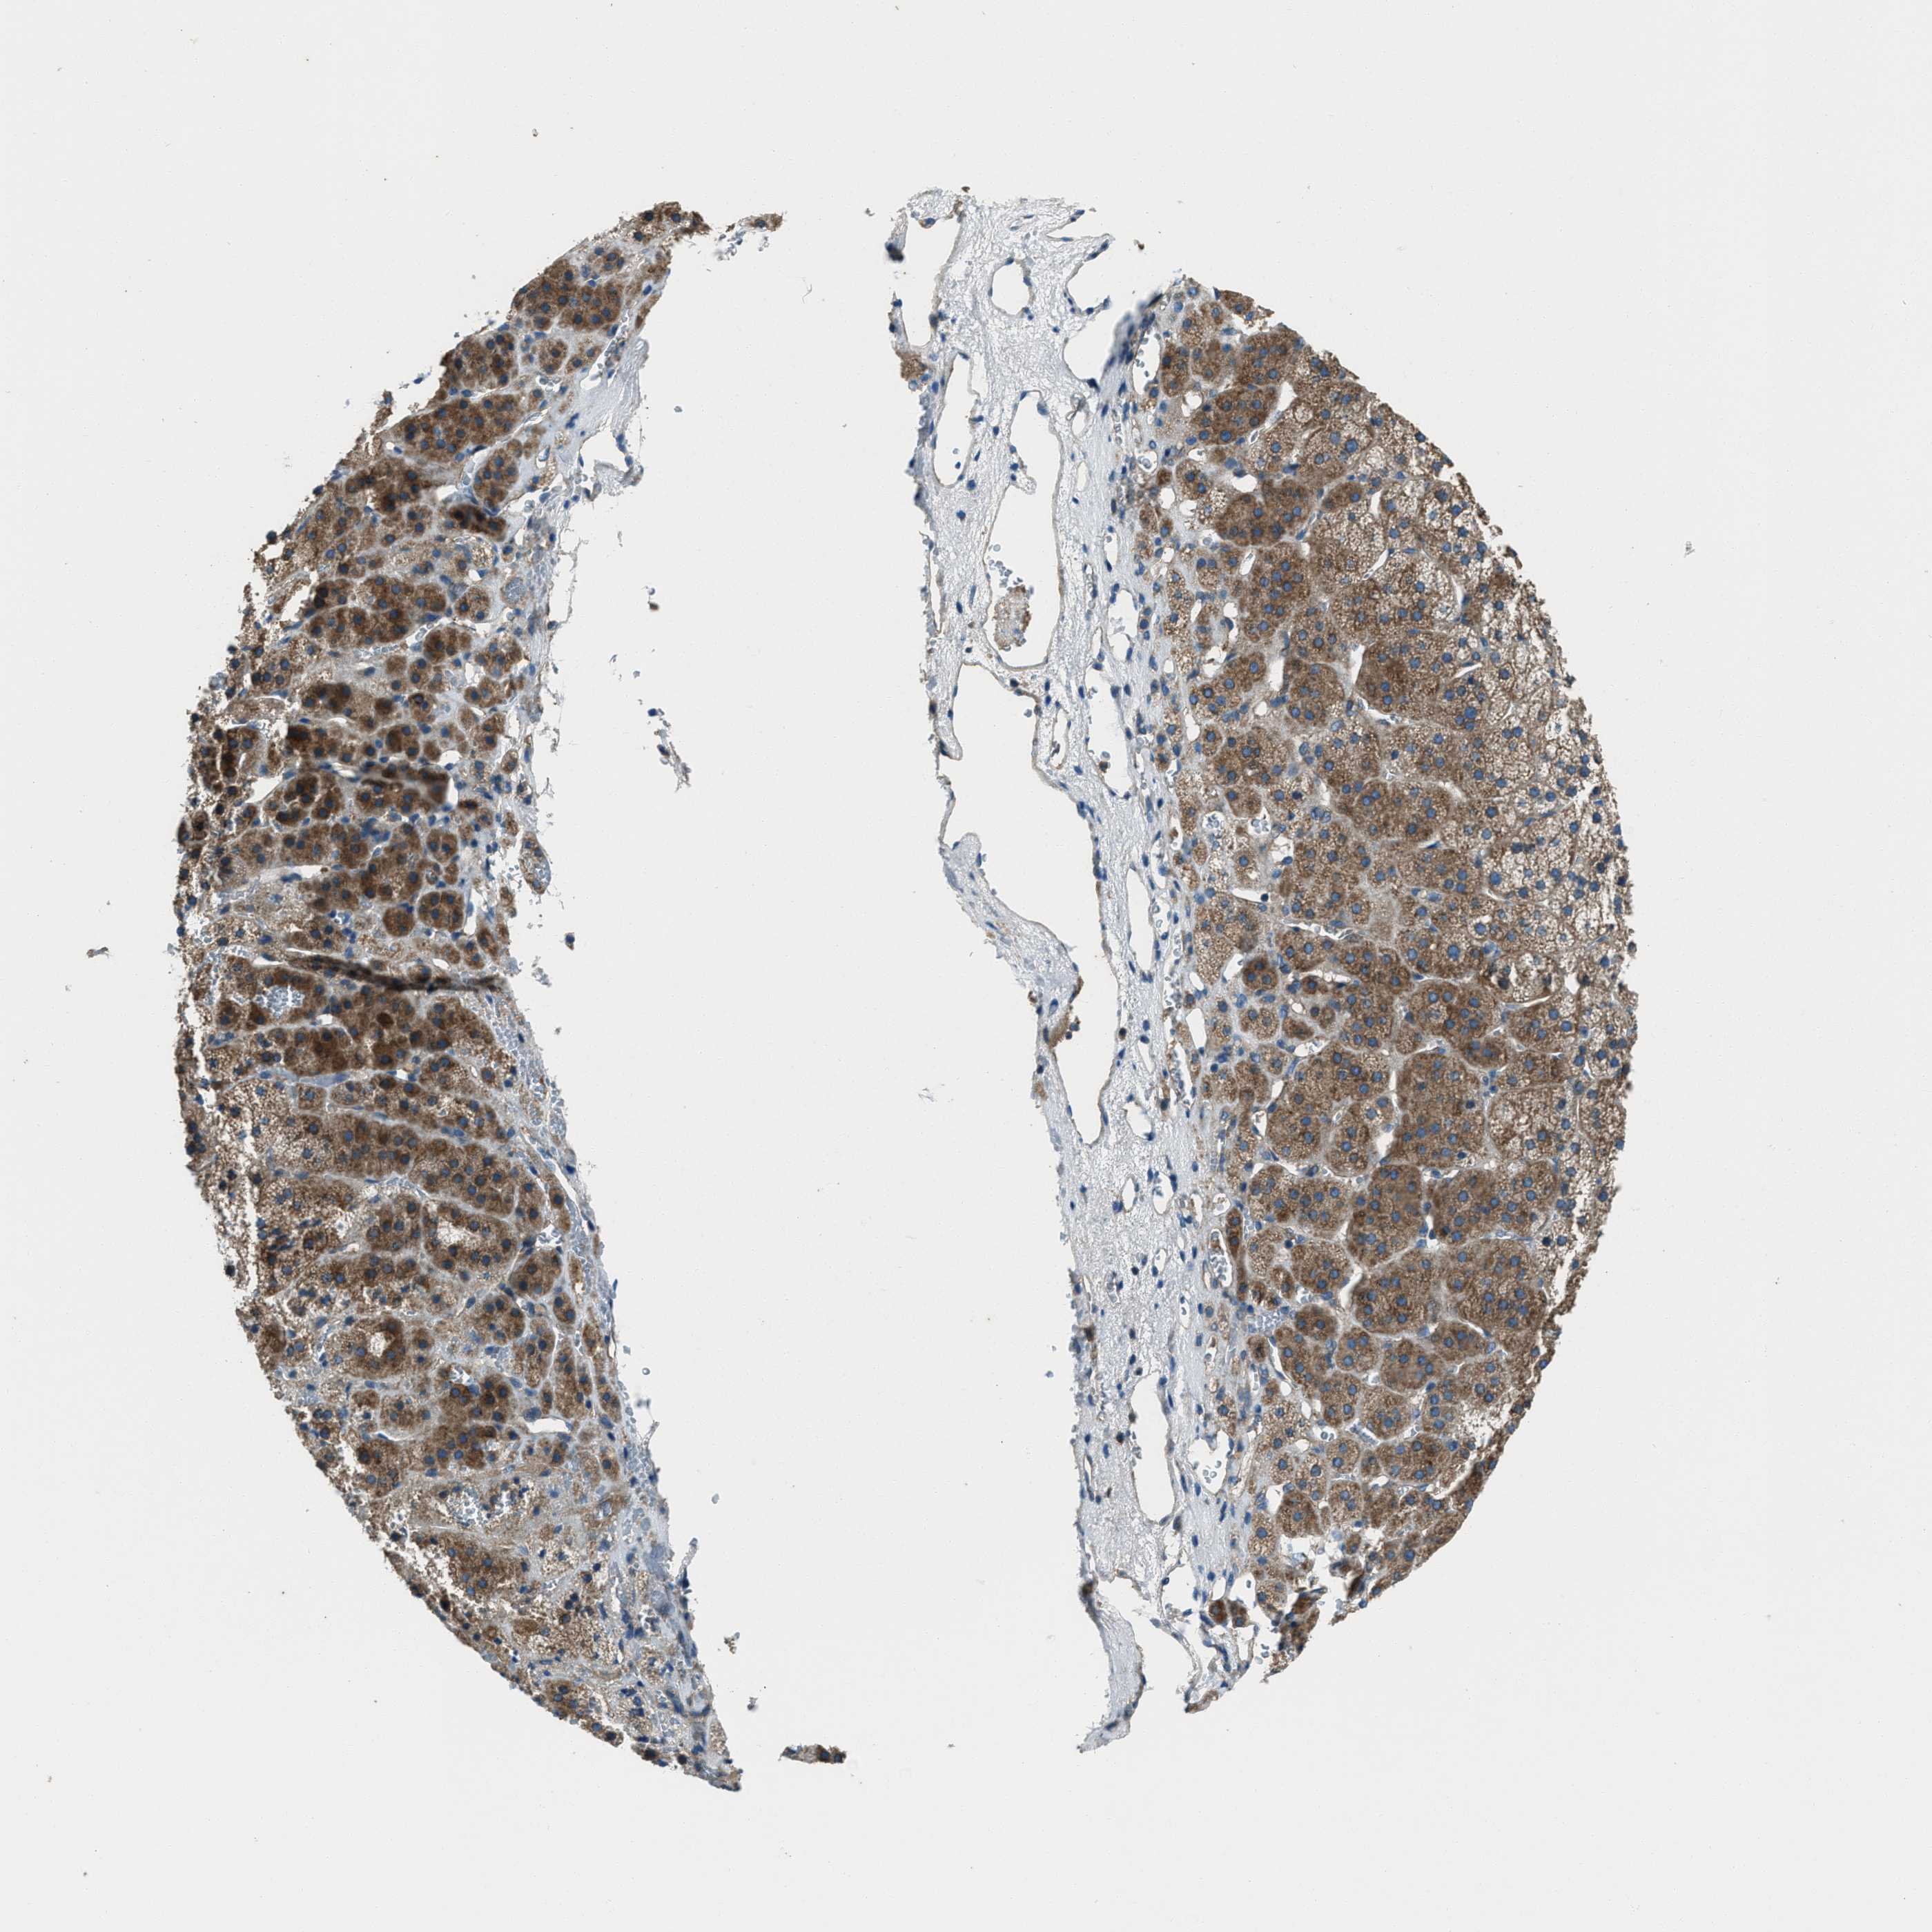

TISSUE PRIMARY DATA ADRENAL GLAND Show tissue menu

ADRENAL GLAND - Antibody stainingi

Antibody staining in the annotated cell types in the current human tissue is reported as not detected, low, medium, or high, based on conventional immunohistochemistry profiling in selected tissues. This score is based on the combination of the staining intensity and fraction of stained cells.

Each image is clickable and will lead to virtual microscopy that enables deeper exploration of all samples and also displays staining intensity scores, fraction scores and subcellular localization as well as patient and tissue information for each sample.

Antibody HPA020095Antibody HPA020138Antibody CAB010878Antibody CAB080402

Glandular cells MediumMediumMediumLow